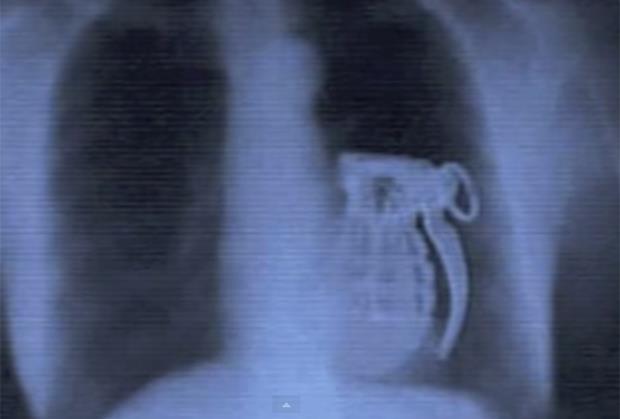

LUDOSTI: 25 najčudnijih stvari koje je rendgen snimio u ljudskom telu